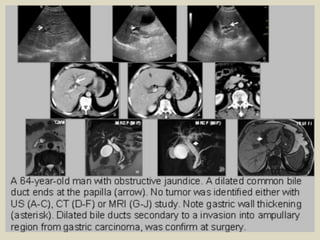

Carcinoma of ampulla of Vater A 64 years old male presented with painless jaundice. Contrast

enhanced CT showed: (a) intra hepatic dilated bile ducts. (b) the ‘double duct’ sign with dilatation of

both the CBD and pancreatic duct, and distension of the gallbladder. (c,d) ampullary mass (arrow).

Carcinoma of ampulla of Vater MRI (e) CoronalT1-FS-Gado, (f) CoronalT2, and (g) MRCP)

showed intrahepatic and common bile ducts dilatation with abrupt distal termination

Carcinoma of ampullaof Vater A 64 years old male presented with painless jaundice. Contrast enhanced CT showed: (a) intra hepatic dilated bile ducts. (b) the ‘double duct’ sign with dilatation of both the CBD and pancreatic duct, and distension of the gallbladder. (c,d) ampullary mass (arrow).

• 53.

Carcinoma of ampullaof Vater MRI (e) CoronalT1-FS-Gado, (f) CoronalT2, and (g) MRCP) showed intrahepatic and common bile ducts dilatation with abrupt distal termination